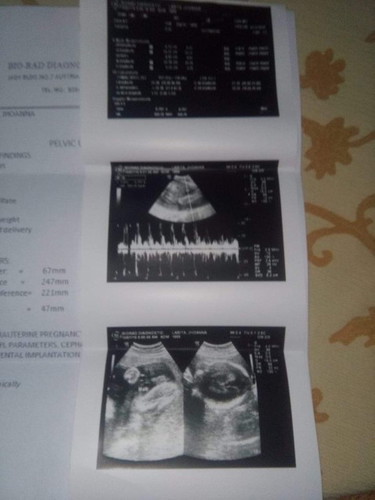

its a Boy!!!! ??

Yey tama kutob q ?? its baby boy. . Thank God?